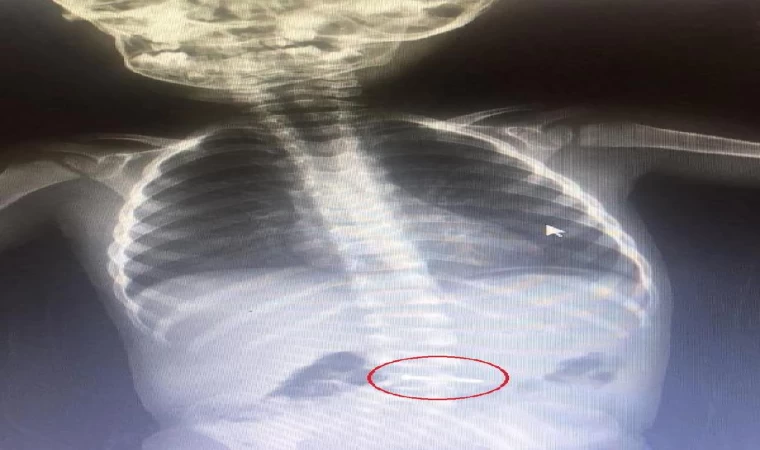

Yavuz YILMAZ/İNEGÖL (Bursa), (DHA)- BURSA’nın İnegöl ilçesinde, oyun oynarken yerde bulduğu çiviyi yutan Asil K. (2), kaldırıldığı hastanede tedaviye alındı.

Olay, saat 10.30 sıralarında Mesudiye Mahallesi Sakin Sokak’ta bulunan bir evde meydana geldi. Asil K., babaannesi mutfaktayken, oyun oynadığı odada yerde bulduğu çiviyi ağzına atarak yuttu. Odaya giren babaanne durumu fark edince, dışarıda olan oğlu ve gelinine haber verdi. Araçla İnegöl Devlet Hastanesi’ne kaldırılan bebek, buradaki tetkiklerinin ardından sevk edildiği, Bursa Yüksek İhtisas Eğitim ve Araştırma Hastanesi’nde tedaviye alındı. Bebeğin yuttuğu çiviyi, doğal yollarla çıkarmasının bekleneceği, aksi takdirde ameliyatla midesinden alınacağı öğrenildi.